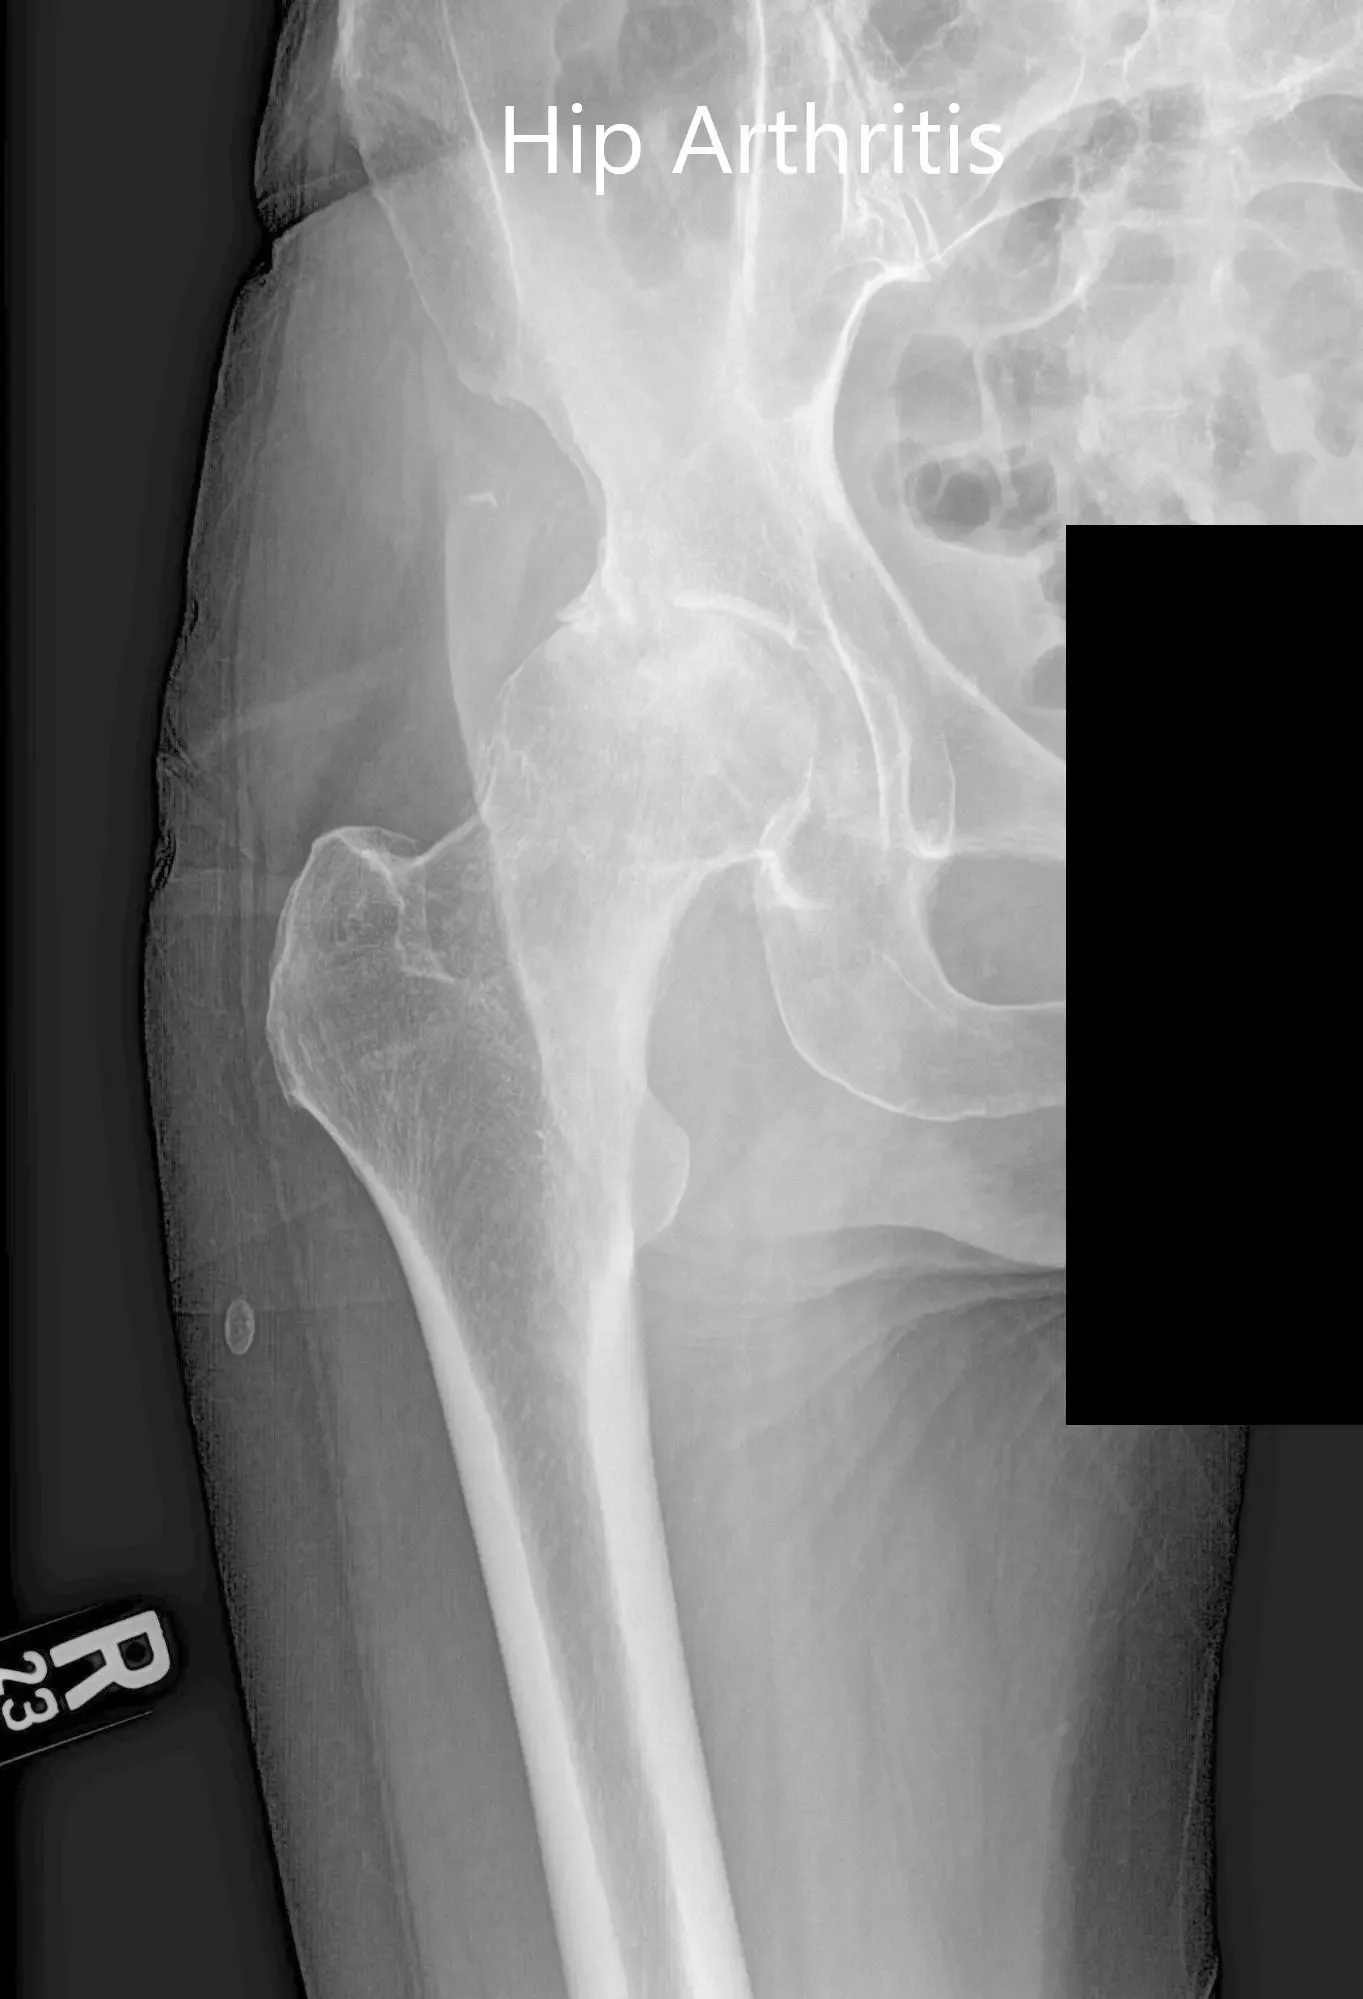

Imaging revealed osteoarthritic changes in bilateral hips (right greater than left). Considering the patient’s comorbidities and lifestyle limiting hip arthritis, he was advised bilateral total hip replacement. Risks, benefits, and alternatives were discussed with the patient at length. He decided to go for right hip replacement first.

Preoperative X-ray of the left hip showing AP and lateral views.